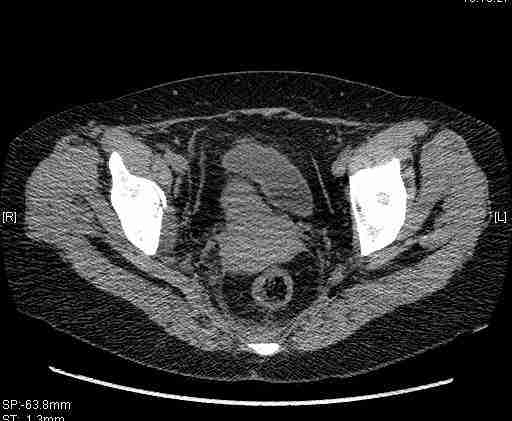

Удалось сегодня вывести пациентку в соседнюю больницу, где есть кт. Срезы сделаны только горизонтальные.

|

Следом 3d

Приветствую,Антон.Рункова рядом нет,но после полученных данных КТ,обсуждали совместно.Итог обсуждения-развернутый ответ дать не получится,т.к.срезы выбраны не информативные.Если ориентироваться на данные 3D,то ,ИМХО,можно лечить на вытяжении.